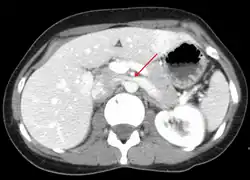

Compression of the left renal vein (marked by the arrow) between the superior mesenteric artery (above) and the aorta (below) due to nutcracker syndrome.